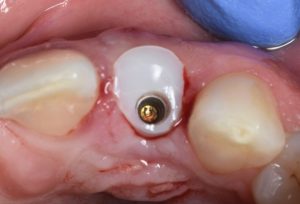

This video demonstrates immediate implant placement in the esthetic zone following atraumatic extraction of a lateral incisor. Emphasis is placed on preserving the hard and soft tissue architecture critical for predictable esthetic outcomes.

The procedure is presented step by step, including minimally traumatic extraction techniques, immediate implant placement, and fabrication and placement of a customized healing abutment to support peri-implant soft tissue contours. Clinical principles for maintaining papillae, controlling the emergence profile, and optimizing soft tissue healing are highlighted.

- Design and placement of customized healing abutments